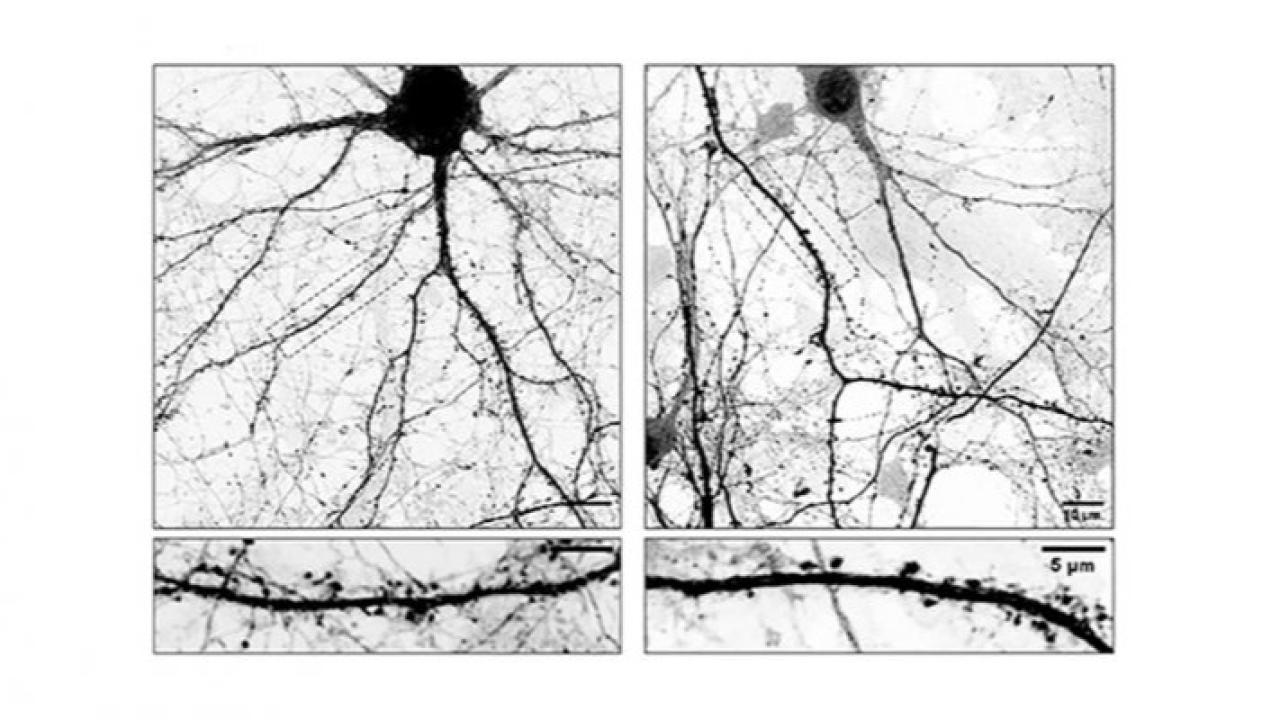

El estudio se enfocó en las neuronas dopaminérgicas, cuya degeneración progresiva es una de las marcas centrales del Parkinson. Los científicos lograron describir procesos que regulan la comunicación neuronal y el mantenimiento de las sinapsis, y cómo su alteración contribuye al deterioro funcional del sistema nervioso.